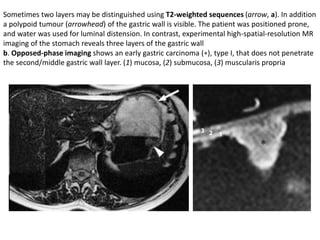

Sometimes two layers may be distinguished using T2-weighted sequences (arrow, a). In addition

a polypoid tumour (arrowhead) of the gastric wall is visible. The patient was positioned prone,

and water was used for luminal distension. In contrast, experimental high-spatial-resolution MR

imaging of the stomach reveals three layers of the gastric wall

b. Opposed-phase imaging shows an early gastric carcinoma (∗), type I, that does not penetrate

the second/middle gastric wall layer. (1) mucosa, (2) submucosa, (3) muscularis propria